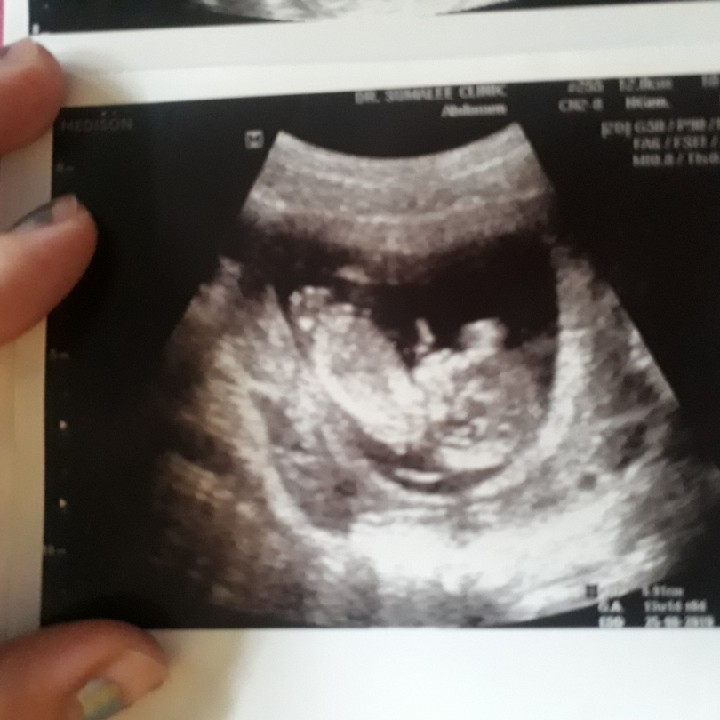

ผช ค่ะ 17 week